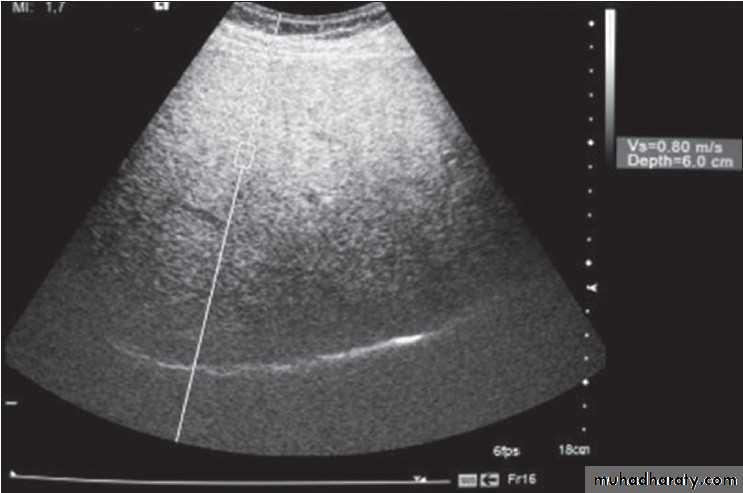

Focal masses ultrasound

Cirrhosis & portal hypertension